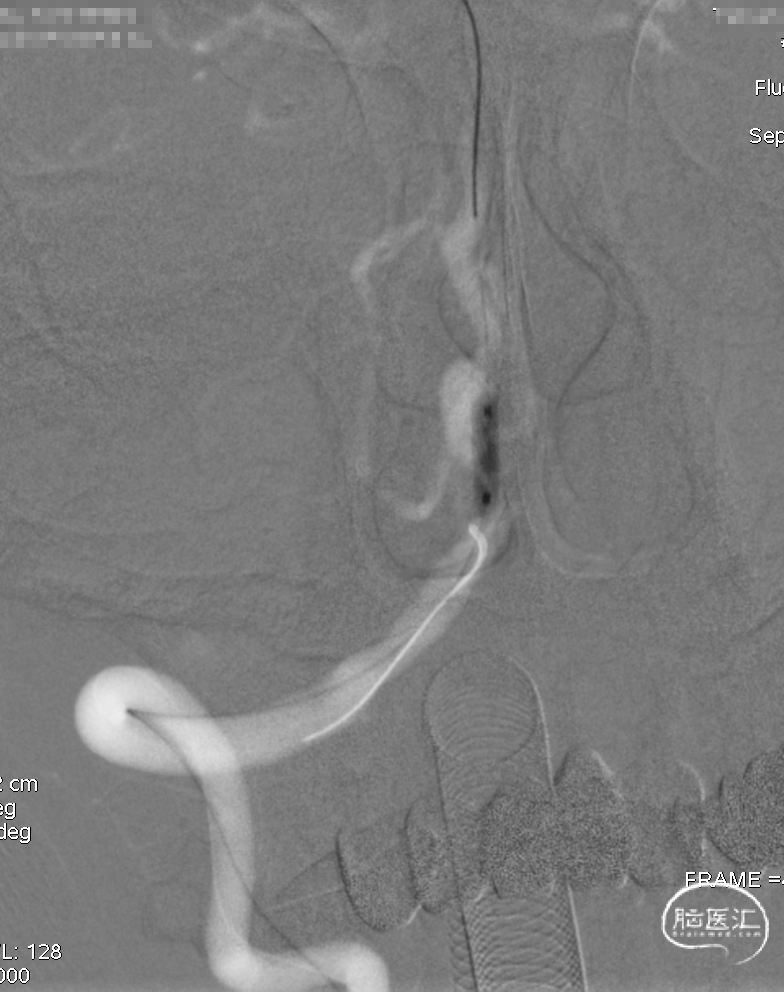

术后即刻DSA。

术后即刻稀释造影:“拉直”可见支架贴壁良好。